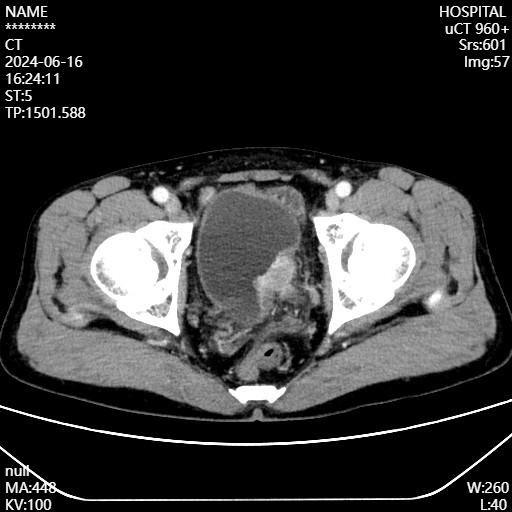

患者王先生(化名)因一年来频繁出现无痛性肉眼血尿,近期还出现腰痛,遂我院泌尿外科就诊,经膀胱镜检查后,被确诊为高级别浸润性膀胱尿路上皮癌。

根据病理检查结果和患者的身体状况,在MDT讨论组经缜密论证后,医生为王先生制定了周全的手术方案,考虑患者左侧输尿管已经被膀胱肿瘤侵犯,合并左肾积水、肾功能不全,且肿瘤面积大,无法施行保留膀胱手术,征求患者及家属意见后,决定采取膀胱根治性切除+回肠膀胱术治疗方案。

膀胱癌的诊断主要依靠影像学检查和内镜检查。超声检查是筛查膀胱癌最常用的检查项目,可以检测膀胱内是否存在肿瘤及其大小、位置等信息。CT检查可以发现较小的肿瘤,并判断邻近器官是否受侵犯及是否存在转移。多参数磁共振成像(mpMRI)则具有出色的软组织分辨率,能够进行肿瘤分期。膀胱镜检查是诊断膀胱癌最可靠的方法,可以直接观察膀胱内的情况,并对可疑病变进行活检以明确病理诊断。